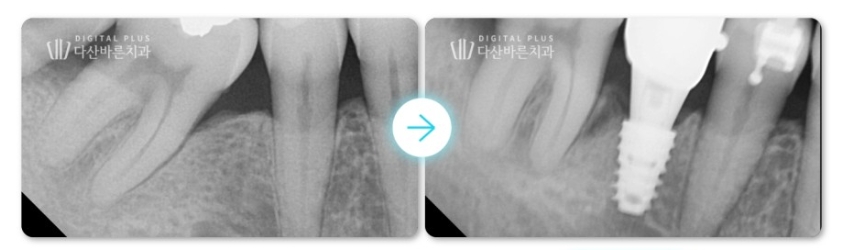

2. 대합치 정출 케이스

두 번째 환자분 케이스입니다. 해당 환자분은 좌측 아래 가장 끝 어금니가

빠진지 오래된 상태셨는데요. 이로 인해 마주하고 있는 위쪽 대합치가

아래쪽으로 정출된 상태가 확인됩니다.

▲ 초진 시 구강 사진. 왼쪽 아래 어금니를 빠진 채 방치하여 위 대합치가 정출된 상태.

우선 위쪽 대합치의 추가적인 정출을 방지하기 위해,

빠진 치아 자리를 대체할 수 있는 임플란트 치료를 먼저 진행합니다.

▲ 위 어금니 추가적인 치아 정출을 방지하기 위해, 아래쪽 빠진 치아 임플란트 치료 먼저 진행.